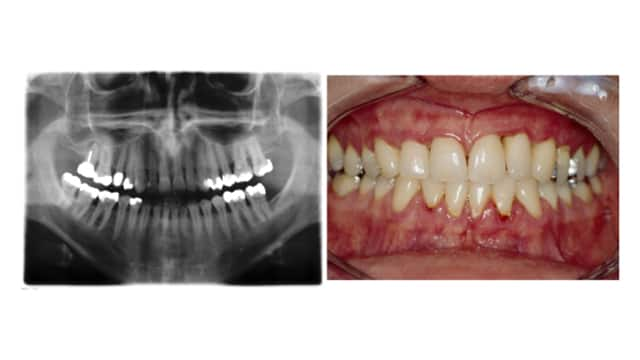

Gum Disease (Gingivitis)

Periodontal Disease

Learn about periodontal disease and the many available options for periodontal disease treatment to help end your periodontal gum disease.

Read More